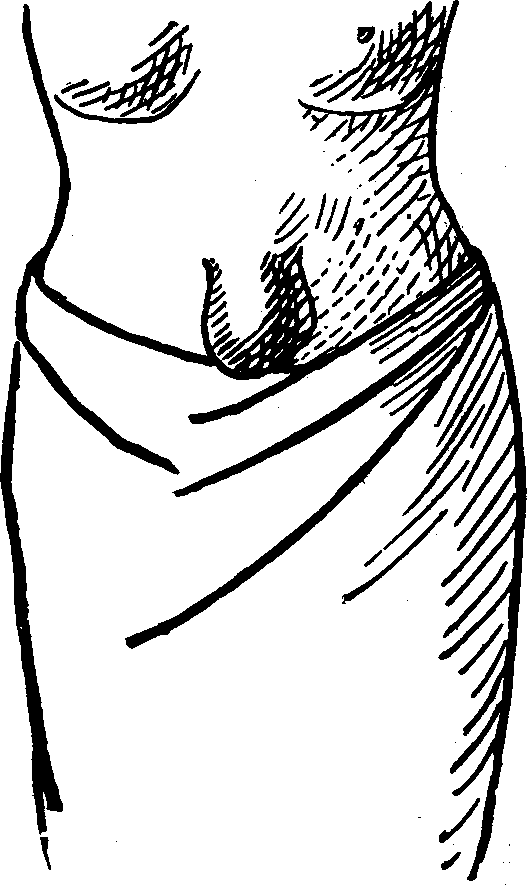

Fig.

24. A representation of the superficial layer of muscles on the anterior

portion of the body.

Fig.

25. A representation of the superficial layer of muscles on the posterior

portion of the body.